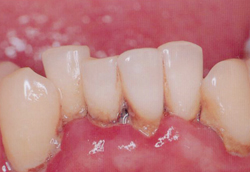

후

치석과 염증이 제거되며 스켈링 전보다 다소 잇몸이 내려가고 치간이 넓어진 느낌에 놀라실 수도 있습니다. 하지만 이는 치석과 염증이 있던 공간이 비워지고 잇몸이 원래의 잇몸뼈 부근으로 자리를 잡으며 생기는 변화입니다.

치석과 염증 등으로 잇몸과 잇몸뼈의 공간이 4mm가량이나 벌어져있던 치료 전과 비교했을 때 치료 후에는 잇몸과 잇몸뼈의 공간이 2~3mm를 유지할 수 있게 됩니다.